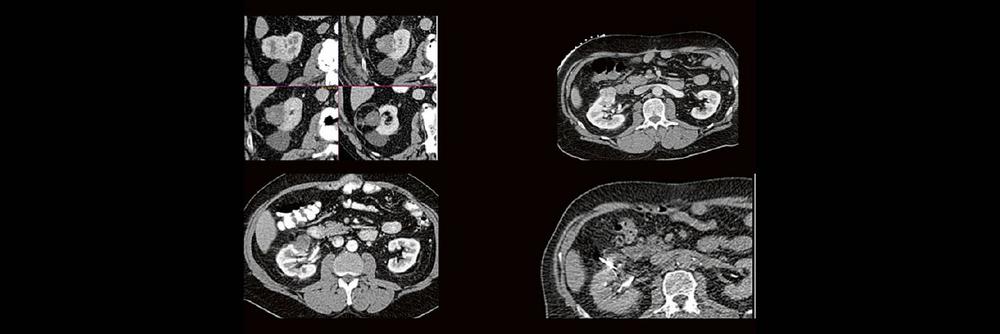

Die Anwendung von ablativen Verfahren hat sich in der klinischen Praxis etabliert. Nierentumoren bieten sich für den Einsatz von RFA und Mikrowelle an. Im Dietrich Bonhoeffer Klinikum Neubrandenburg blicken wir auf 15 Jahre Erfahrung mit mehr als 100 RFA/Mikrowellenablationen von Nierentumoren zurück. Im Vortrag werden die eigenen Erfahrungen und Ergebnisse vorgestellt.

Dabei wird auf die Indikationsstellung, Vorbereitung, Durchführung, Nachuntersuchungsintervall, Komplikationen und Erfolgsrate eingegangen.

Back to the roots! Gute Kenntnisse der Anatomie sind der Schlüssel zur guten Planung, Durchführung und richtigen Diagnosestellung im CT des Abdomens. Lernen sie unverkrampft

- richtiges Kontrastmittel-Timing im Bild erkennen

- Anatomie in Pathologie übersetzen

Haben Sie es erkannt? Probieren Sie selbst im lockeren Fallquiz zum mitraten.